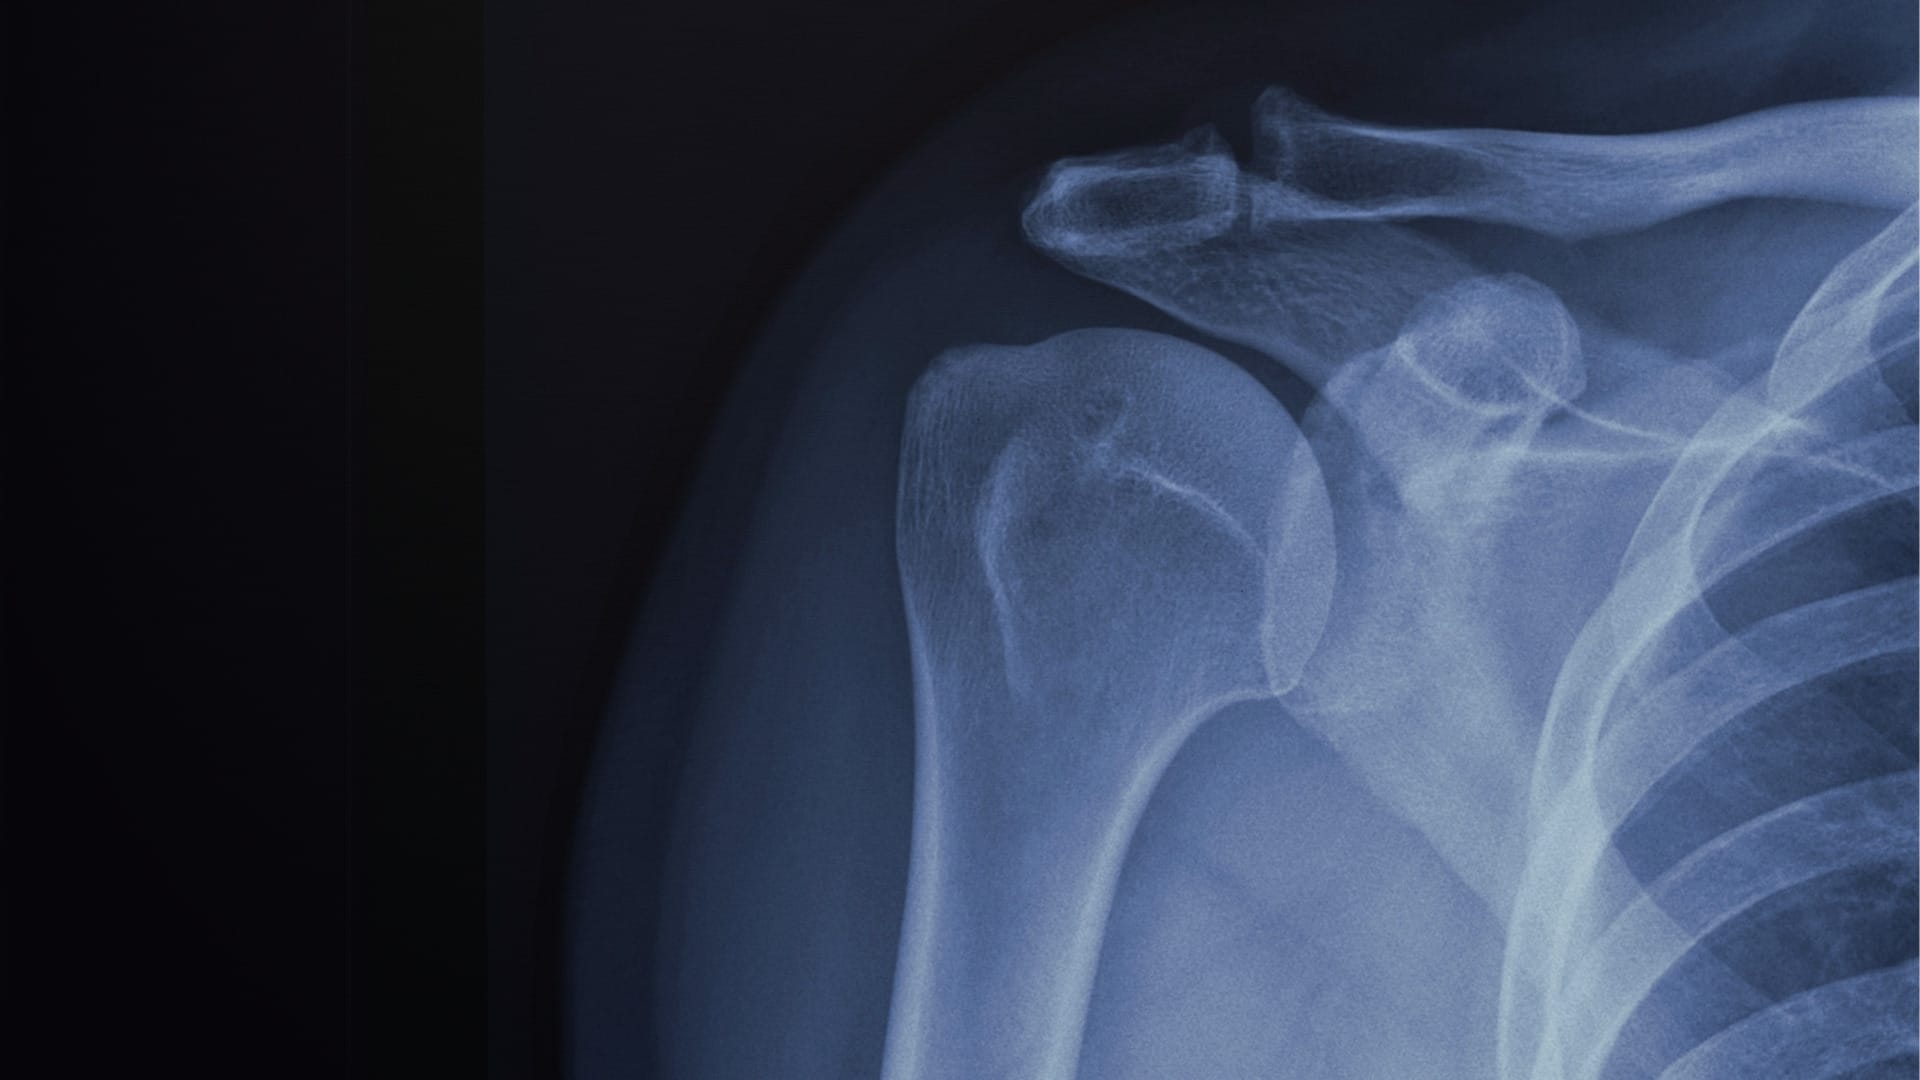

When calcium crystals accumulate in these tendons, they can form small deposits that may be visible on imaging tests such as X-rays or ultrasound. These deposits may remain small and asymptomatic, or they may lead to pain and inflammation.

Calcification most commonly occurs in the supraspinatus tendon, one of the key rotator cuff tendons responsible for lifting the arm. Although the presence of calcium deposits may sound alarming, they are usually part of a benign process rather than a dangerous one.